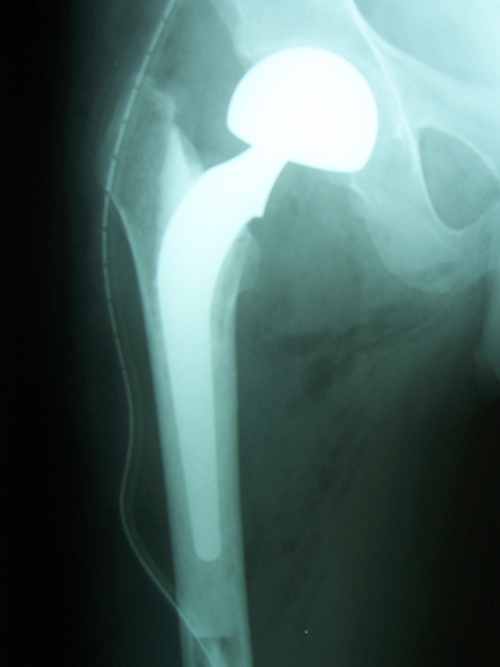

Case:3 Septic Arthritis-THR

Arthroscopy Surgeon in Ahmedabad|Spine Best doctor

2Months Pre-Op

Arthroscopy Surgeon in Ahmedabad|Sports Injuries Doctor in Ahmedabad

Imm Post-Op

Arthroscopy Surgeon in Ahmedabad|Joint Replacement

Total Hip Replacement